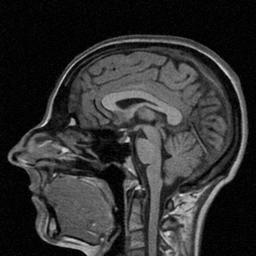

Magnetic Resonance Imaging (MRI) is one of the most dynamic and safe imaging techniques available for clinical applications. However, the rather slow speed of MRI acquisitions limits the patient throughput and potential indi cations. Compressive Sensing (CS) has proven to be an efficient technique for accelerating MRI acquisition. The most widely used CS-MRI model, founded on the premise of reconstructing an image from an incompletely filled k-space, leads to an ill-posed inverse problem. In the past years, lots of efforts have been made to efficiently optimize the CS-MRI model. Inspired by deep learning techniques, some preliminary works have tried to incorporate deep architectures into CS-MRI process. Unfortunately, the convergence issues (due to the experience-based networks) and the robustness (i.e., lack real-world noise modeling) of these deeply trained optimization methods are still missing. In this work, we develop a new paradigm to integrate designed numerical solvers and the data-driven architectures for CS-MRI. By introducing an optimal condition checking mechanism, we can successfully prove the convergence of our established deep CS-MRI optimization scheme. Furthermore, we explicitly formulate the Rician noise distributions within our framework and obtain an extended CS-MRI network to handle the real-world nosies in the MRI process. Extensive experimental results verify that the proposed paradigm outperforms the existing state-of-the-art techniques both in reconstruction accuracy and efficiency as well as robustness to noises in real scene.

Magnetic Resonance Imaging (MRI) is widely utilized in clinical applications because of its none-invasive property and excellent capability in revealing both functional and anatomical information. However, one of the main drawbacks is the inherently slow acquisition speed of MRI in k-space (i.e., Fourier space), due to the limitation of hardwares (?). Compressive sensing MRI (CS-MRI) is a commonly used technique allowing fast acquisition at data sampling rate much lower than Nyquist rate without deteriorating the image quality.

| Ground Truth (PSNR) | Zero-filling (22.33) | TV (25.22) | SIDWT (25.10) | PBDW (27.39) | |

| PANO (28.77) | FDLCP (29.78) | ADMM-Net (27.91) | BM3D-MRI (29.35) | Ours (30.48) |

| Ground Truth (PSNR) | PANO (27.73) | FDLCP (26.84) | BM3D-MRI (26.27) | Ours (28.22) |